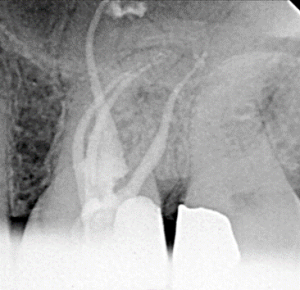

Root Canal / Retreatment

Clinical Cases